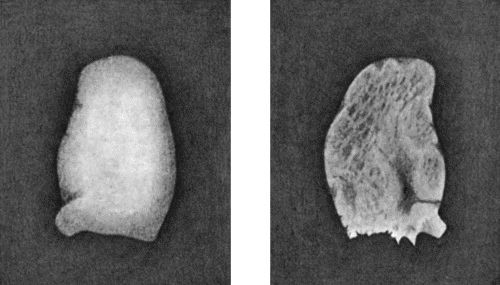

540 167.Loose Body from Knee-joint

541 168.Multiple partially ossified Chondromas of Synovial Membrane from Shoulder-joint

542 169.Multiple Cartilaginous Loose Bodies from Knee-joint

543MANUAL OF SURGERY